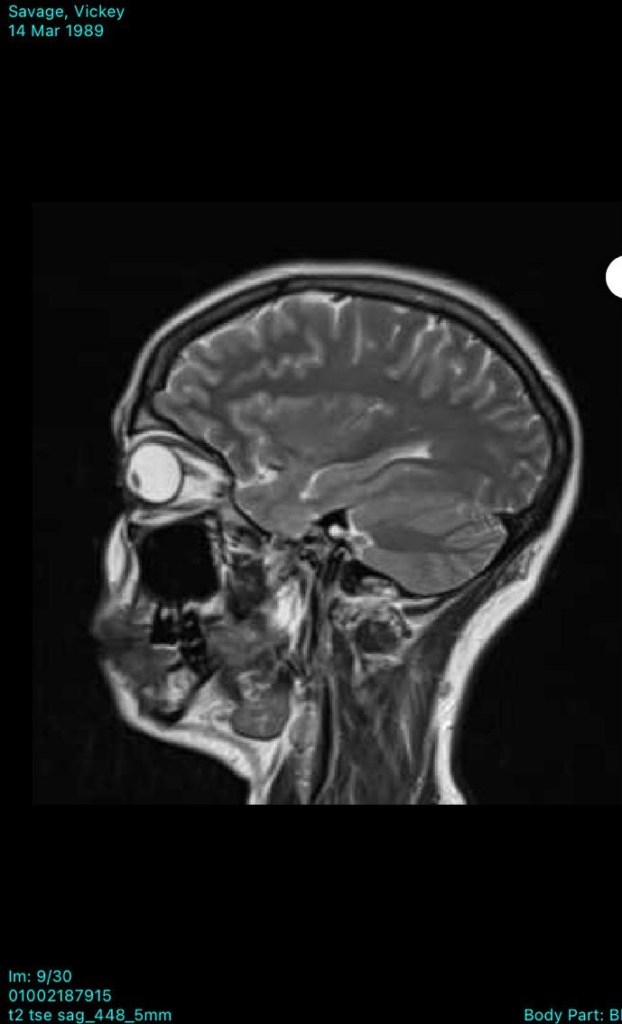

In December 2022, we later found out that there was a 13 mm cystic lesion on her pineal gland, in the limbic area of the brain, left sided. Below you will see her MRI scans from showing the cyst.

The pineal cyst in her mid brain has decreased in size, which they are also blown away by. The cyst was causing irritation to brain tissue and nerves. All physiologically induced via constant mobilisation of stressors! Through bringing down her sympathetic levels, signalling the Vagus Nerve, and inducing anti inflammatory and anti aging responses, this has been the outcome.